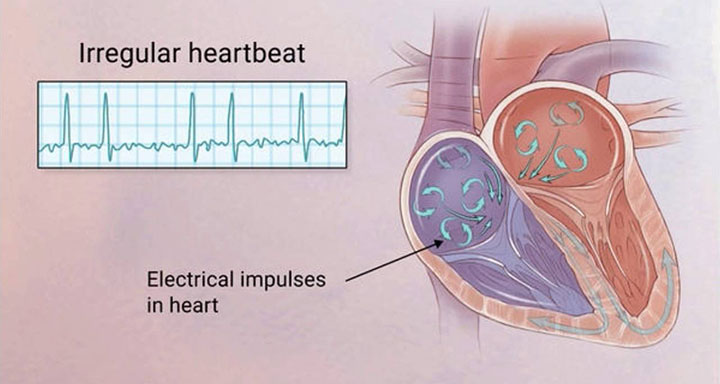

Atrial Fibrillation is a medical condition characterized by irregular, rapid heart rhythm. It primarily affects the atria, which are the two upper chambers of the heart. The arrhythmia, an irregular rhythm, is caused by abnormal electrical impulses in the heart due to a lack of coordination in atrial activity....